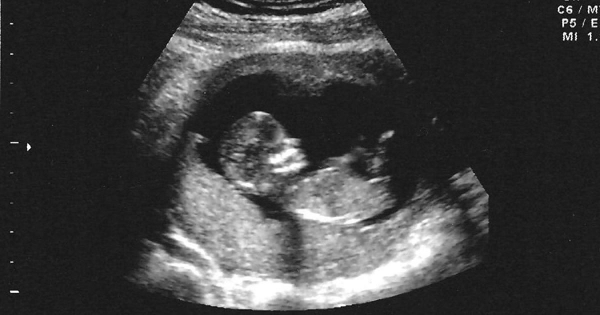

婦科醫生發現來婦產科的17歲小女生已懷孕14週,但看著超音波圖,卻說不出恭喜!

而當超音波探頭一放下去後,發現嬰兒已經14週了,「和平常不同的是,『恭喜』兩個字我實在說不出口。」